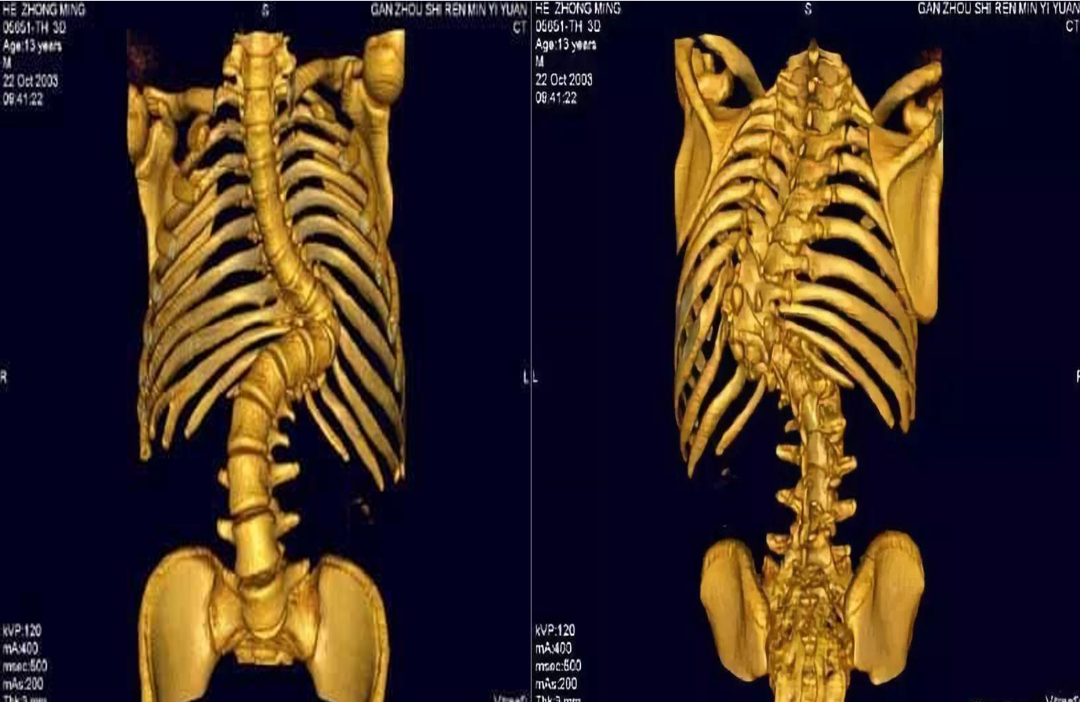

脊柱侧弯又称脊柱侧凸,它是一种脊柱的三维畸形,包括冠状位、矢状位和轴位上的序列异常。

正常人的脊柱从后面看应该是一条直线,并且躯干两侧对称。如果从正面看有双肩不等高或后面看到有后背左右不平,就应怀疑“脊柱侧凸”。这个时候应拍摄站立位的全脊柱X线片,如果正位X线片显示脊柱有大于10度的侧方弯曲,即可诊断为脊柱侧凸。轻度的脊柱侧凸通常没有明显的不适,外观上也看不到明显的躯体畸形。较重的脊柱侧凸则会影响婴幼儿及青少年的生长发育,使身体变形,严重者可以影响心肺功能、甚至累及脊髓,造成瘫痪。轻度的脊柱侧凸可以观察,严重者需要手术治疗。

当初步怀疑有脊柱侧弯时, X线脊柱全长检查是明确诊断的重要检查,此项检查可以明确脊柱具体侧弯角度。进一步出现脊髓压迫症状,怀疑椎体、椎间盘病变时,则需要加做脊柱全长CT或脊柱全长MRI,明确病变情况。